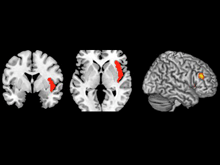

Оказалось, все дело в нарушении механизма связи двух областей мозга - боковой фронтальной коры и островка головного мозга, передает Wellcome Trust.

Это открытие было сделано после того, как ученые просканировали мозг 35 здоровых добровольцев и 38 шизофреников. Именно вторая группа не могла переключаться между двумя областями мозга. То есть у шизофреников не происходила требуемая активация фронтальной коры и возвращение в реальность. Островок должен стимулировать кору, а кора, в свою очередь, должна снижать активность островка. Но у шизофреников система не работала.